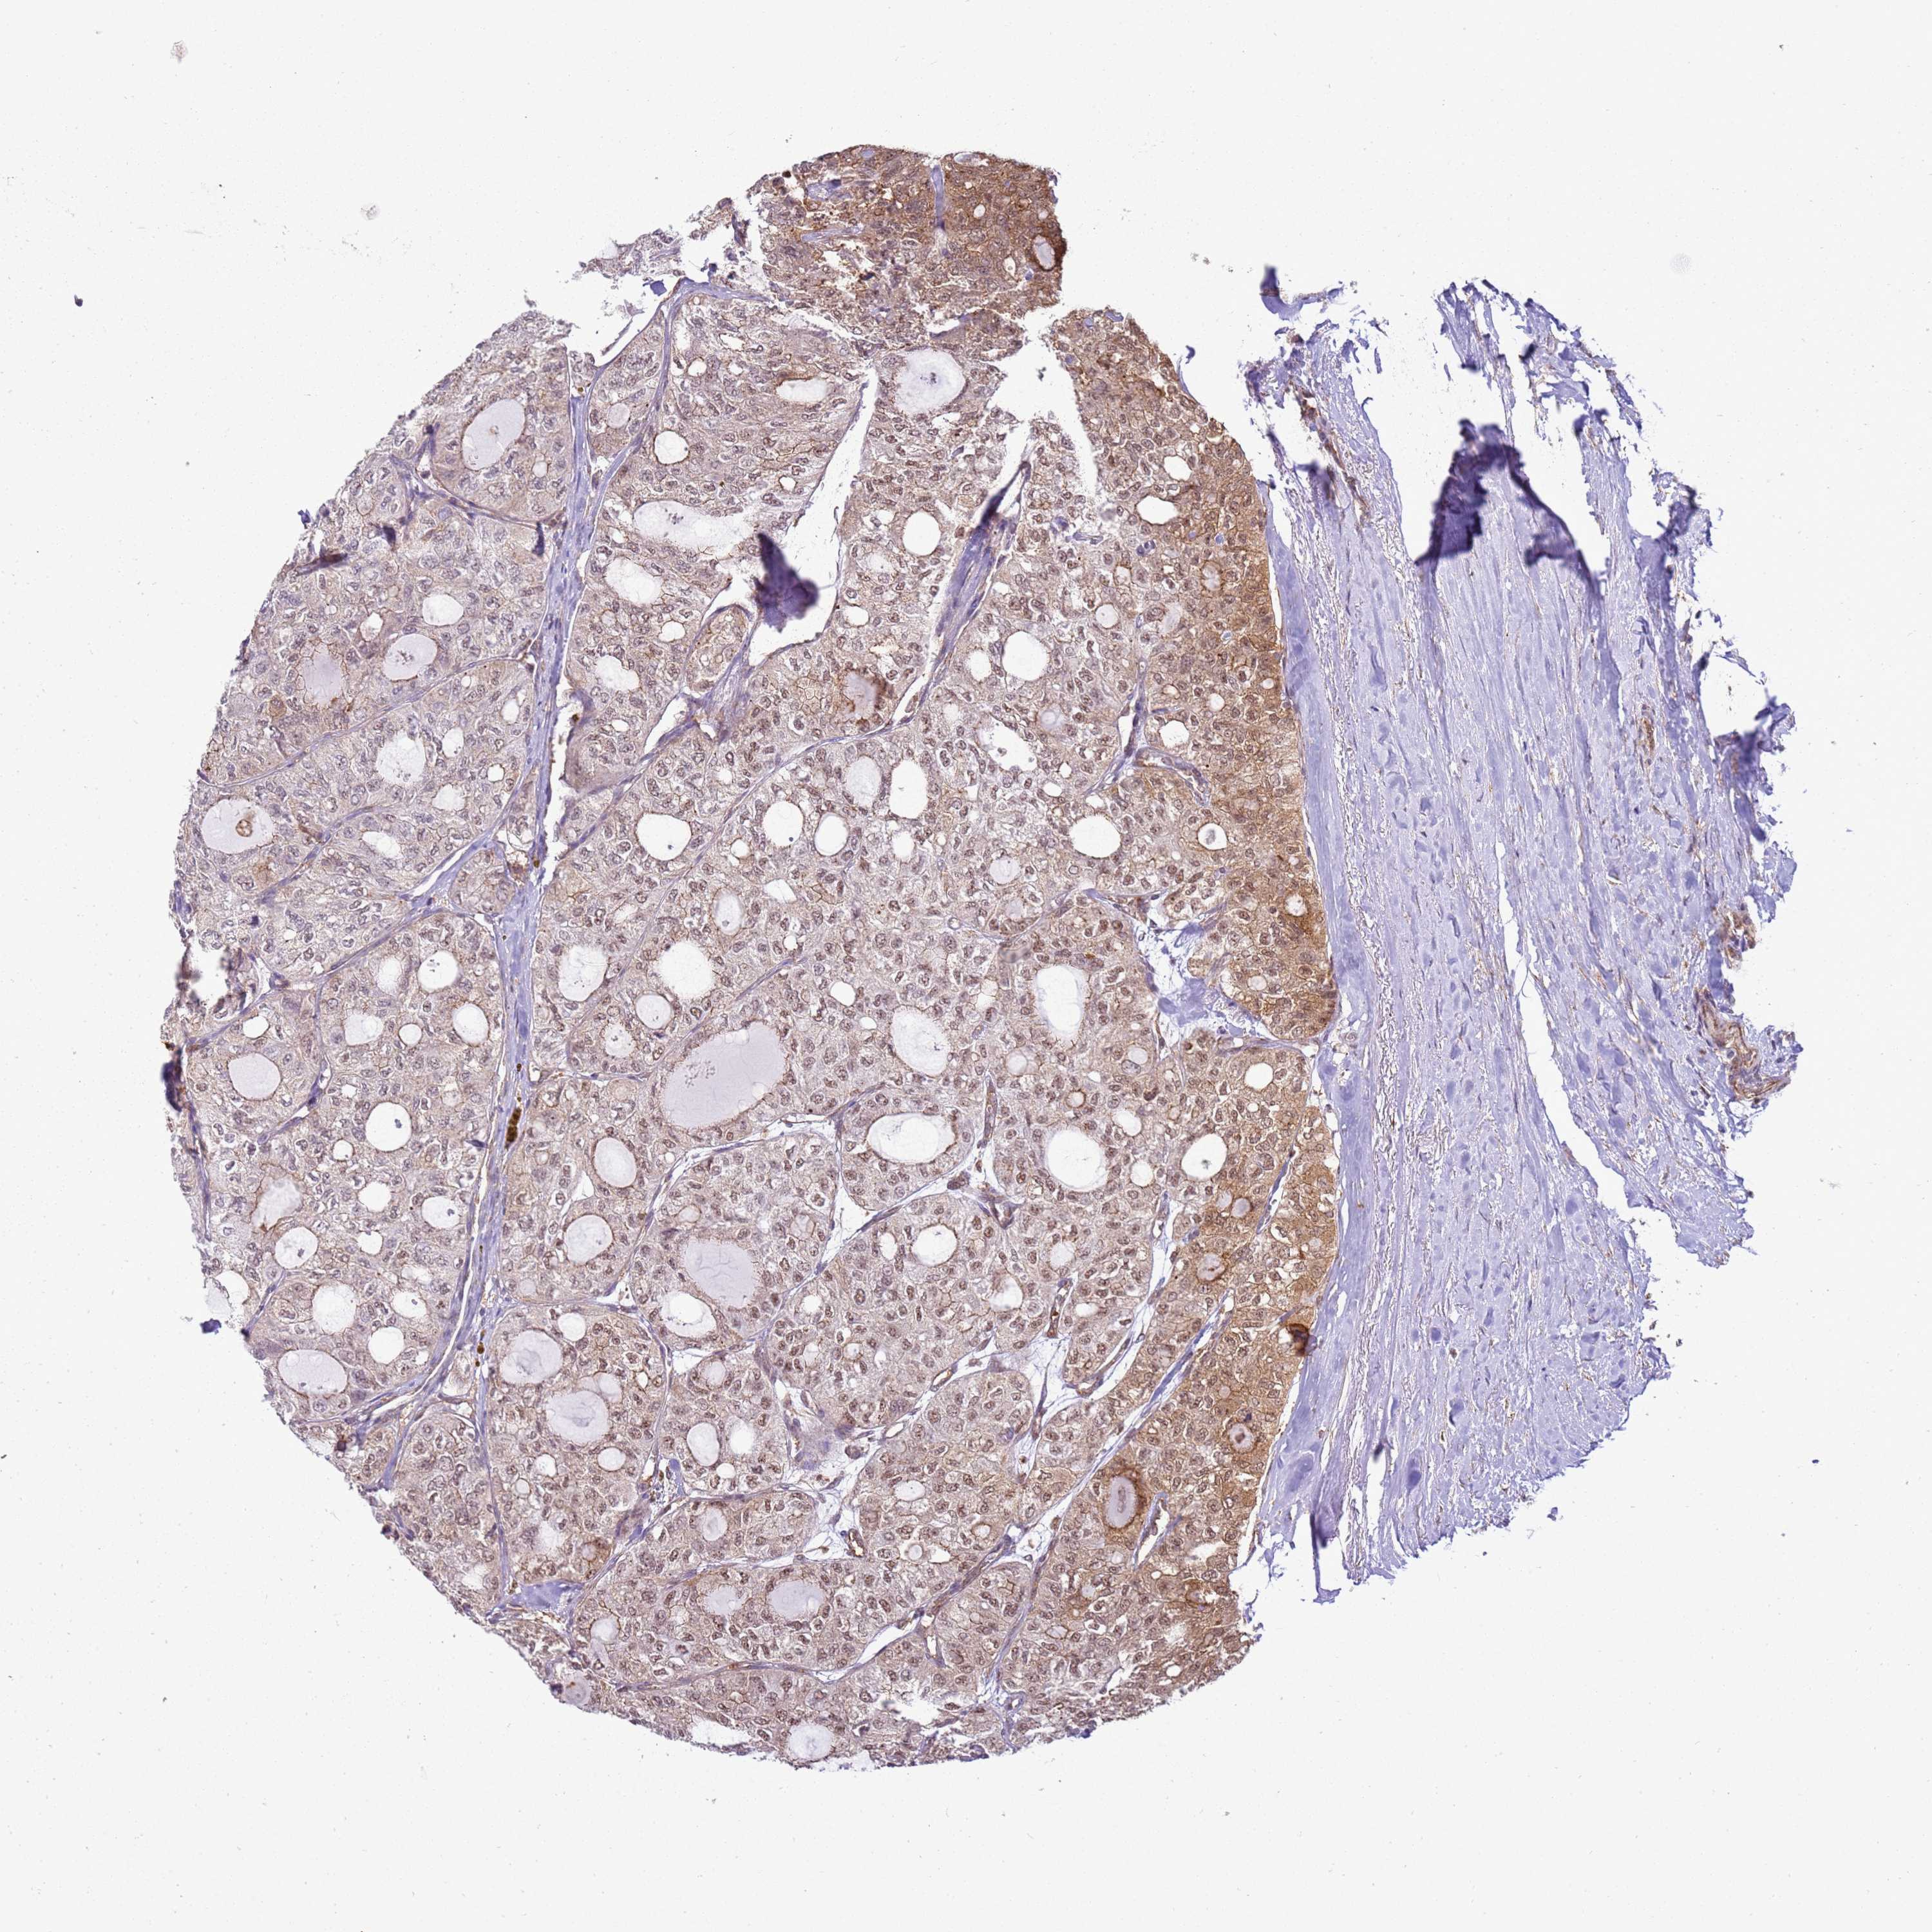

THYROID CANCER - Protein expressioni

A mouse-over function shows sample information and annotation data. Click on an image to view it in a full screen mode. Samples can be filtered based on level of antibody staining by selecting one or several of the following categories: high, medium, low and not detected. The assay and annotation is described here.

Note that samples used for immunohistochemistry by the Human Protein Atlas do not correspond to samples in the TCGA dataset.

Antibody stainingi

Antibody staining in the annotated cell types in the current human tissue is reported as not detected, low, medium, or high, based on conventional immunohistochemistry profiling in selected tissues. This score is based on the combination of the staining intensity and fraction of stained cells.

Each image is clickable and will lead to virtual microscopy that enables deeper exploration of all samples and also displays staining intensity scores, fraction scores and subcellular localization as well as patient and tissue information for each sample.

Antibody HPA045918

Staining

High

Medium

Low

Not detected

Intensity

Strong

Moderate

Weak

Negative

Quantity

>75%

75%-25%

<25%

None

Location

Nuclear

Cytoplasmic/membranous

Cytoplasmic/membranous,nuclear

Papillary adenocarcinoma, NOS

Follicular adenoma carcinoma, NOS